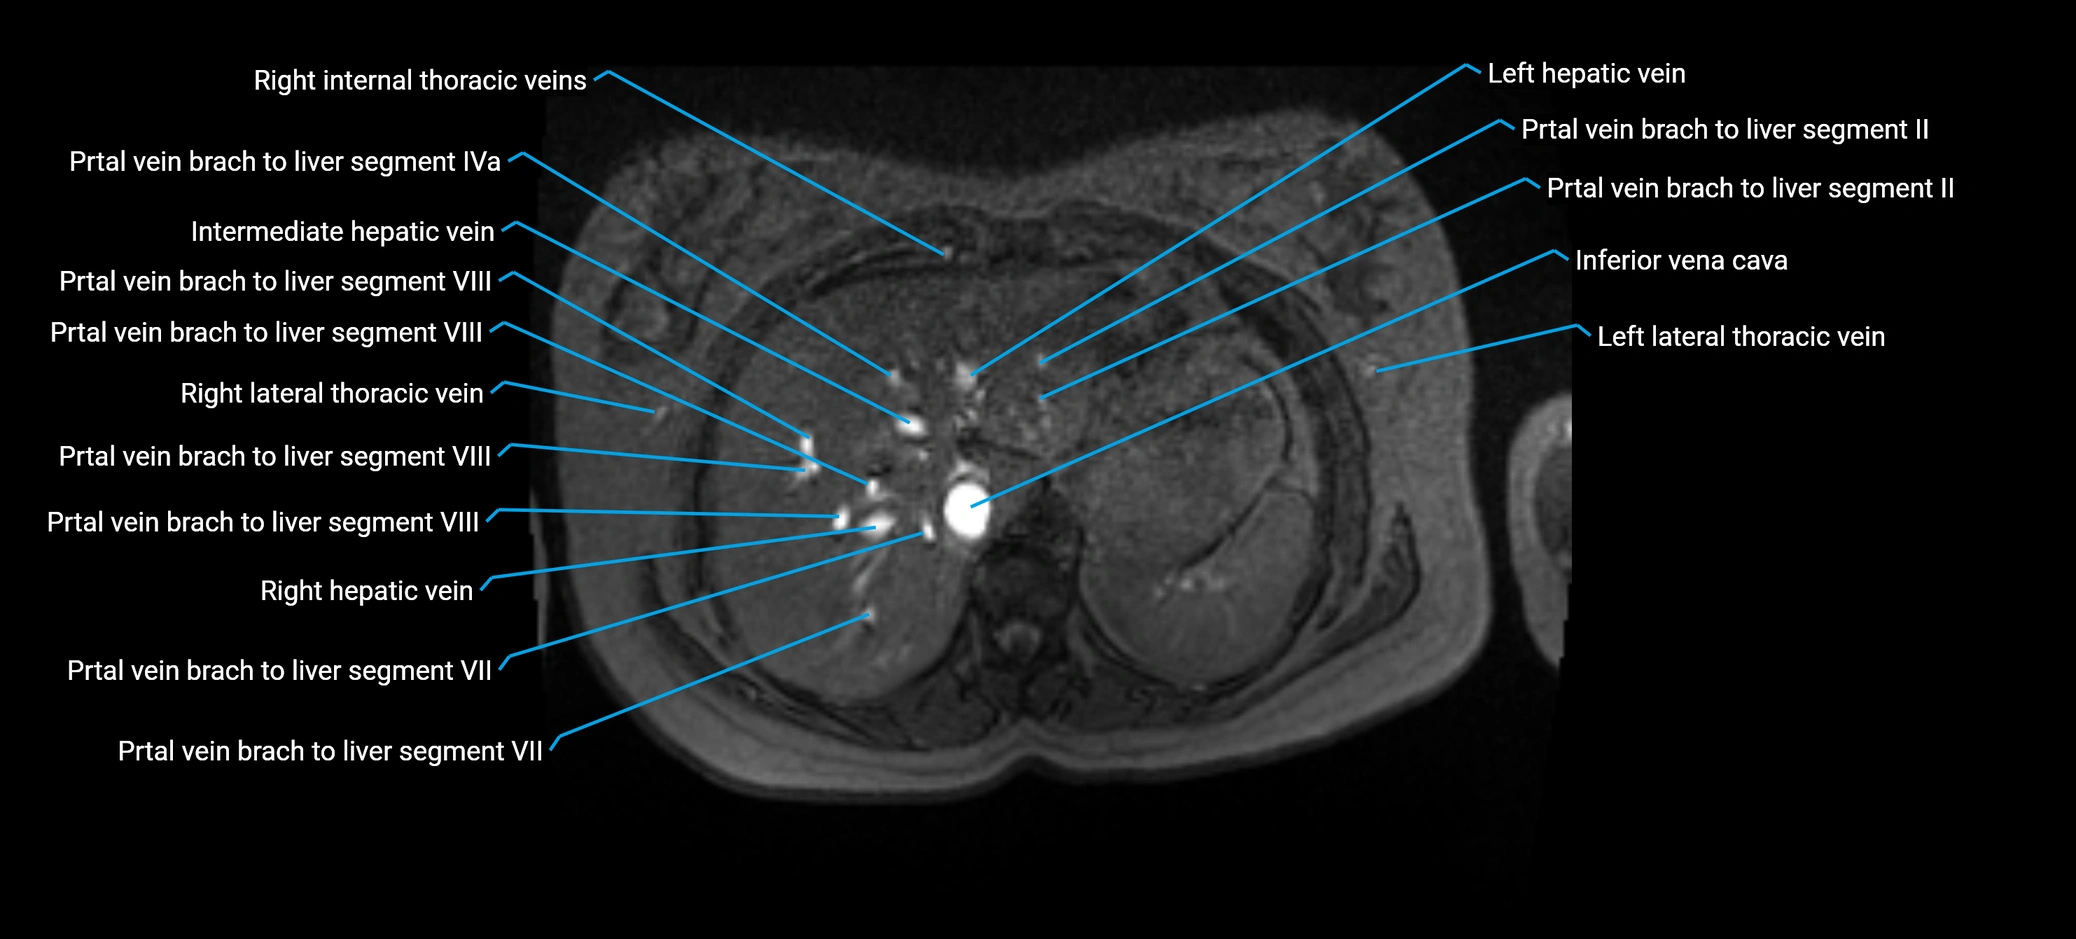

MRV TOF (Time-of-Flight MR Venography):

• Appears as a bright, high-signal vascular channel representing flowing blood

• Clearly shows branching pattern of right portal vein into anterior and posterior branches

• Best in coronal or axial reconstructions for segmental mapping

• No need for contrast, relies on flow-related enhancement

Post-Contrast T1 Fat-Sat GRE:

• Enhances brightly and homogeneously during the portal venous phase

• Clearly delineates branching into segments V and VIII

• Best sequence for evaluating patency, caliber, and anatomic variants